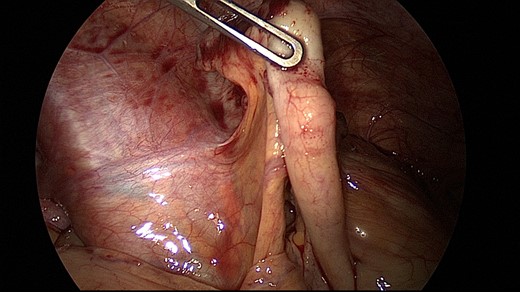

A 26-year-old nulliparous woman presented with right lower and upper abdominal pain 3 days after laparoscopic right ovarian cystectomy (dermoid ovarian cyst) and myomectomy of a small subserous myoma. Intraoperatively, the abdominal organs including the appendix appeared inconspicuous (Fig. 1). She was discharged from the hospital with more abdominal pain than expected, but still in a normal range. The pain increased on her second postoperative day in the evening and the next day, it became severe with concomitant nausea and vomiting.

Physical examination revealed normal vital signs, severe diffuse right abdominal tenderness, generalized rebound tenderness, guarding accentuated in the right lower abdomen and rare bowel movements. Laboratory evaluation showed a slightly elevated C-reactive protein (CRP) (17 mg/l, reference <5 mg/l) and an elevated leukocyte count (18 000 cell/mm3, reference <10 200 cell/mm3). Transvaginal and transabdominal ultrasound scanning revealed a normal uterus, a small fluid collection in the Douglas space, an already normal-appearing right ovary, no free fluid in the Morison’s pouch, no pathology of the gallbladder and no lesions suspected to be an abscess. But it showed an increased diameter of the appendix of 8.2 mm, “target sign” on axial scan of the appendix, an appendicolith and periappendiceal fluid of ~2 ml (Fig. 2). Therefore, an immediate re-laparoscopy was indicated, which showed an acute appendicitis and peritonitis (Fig. 3). A laparoscopic appendectomy was performed. The postoperative period was uneventful and the patient was discharged without complication. Pathologic evaluation of the appendix showed an ulcero-phlegmonous, partly abscessing appendicitis, a distal appendicolith of 0.5 cm in diameter and acute peritonitis.